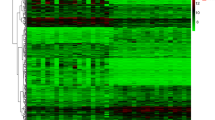

1606 DEGs were screened between POAG patients and healthy controls using the “limma” package. Compared with datasets obtained from gutMGene v1.0, a total of 16 differentially expressed GM-related genes in POAG patients were identified after taking the intersection of the Venn, including 9 common upregulated genes and 7 common downregulated genes. These genes were identified as GM-related DEGs in POAG (Fig. 2 and Table 2).

Differentially expressed gut microbiota-related genes in POAG patients and normal control. A The heatmap of 16 differentially expressed GM-related genes in POAG patients. Red represents upregulated genes and blue represents downregulated genes. GM, gut microbiota, B volcano plot of 16 differentially expressed GM-related genes in POAG patients. The red dots in the picture represent significantly upregulated genes, blue dots represent significantly downregulated genes, black dots represent genes that are not differentially expressed, and the five genes that are most significantly upregulated or downregulated are marked; C a total of 201 differentially expressed GM-related genes shown in Venn diagram; D the boxplot of 16 differentially expressed GM-related genes in POAG and normal control, including 9 upregulated genes and 7 downregulated genes